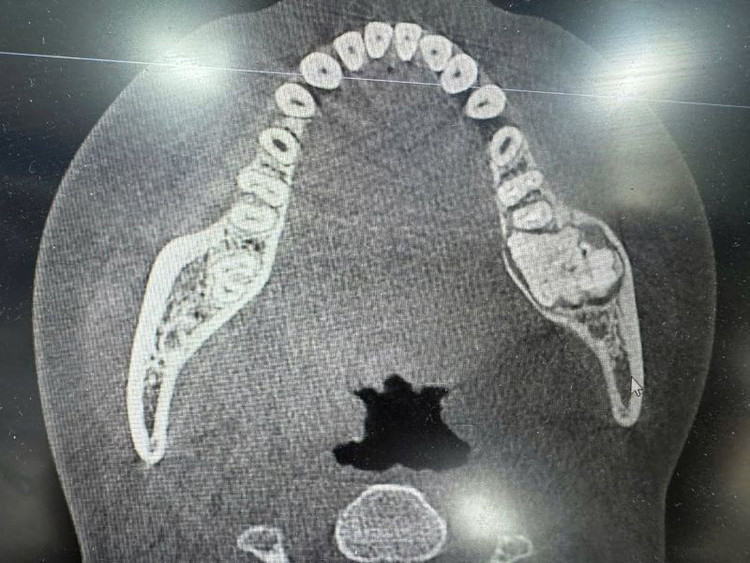

Khối u men răng trên phim chụp - Ảnh BVCC

TS.BS Nguyễn Quang Đức, Trung tâm Phẫu thuật sọ mặt và tạo hình, Bệnh viện Trung ương Quân đội 108 cho biết, u men răng không phải là loại bệnh hiếm gặp, chiếm 6% các loại u về răng hàm mặt, nhưng hầu như người dân không biết. Bệnh rất khó được phát hiện bởi khối u không gây đau nhức, tiến triển âm thầm, chỉ đến khi bị sưng, bị lệch mặt, răng lung lay... đi khám may chăng mới phát hiện được.